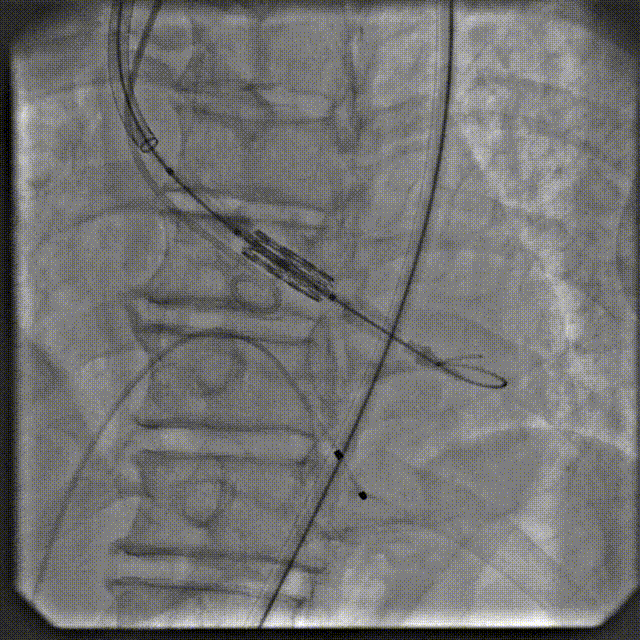

手术过程

根部造影

跨瓣

定位造影

球扩

释放

最终造影

术后复查造影示瓣膜位置满意,形态良好,冠脉显影良好;TTE示轻微瓣周漏;排除入路血管问题,手术圆满成功。